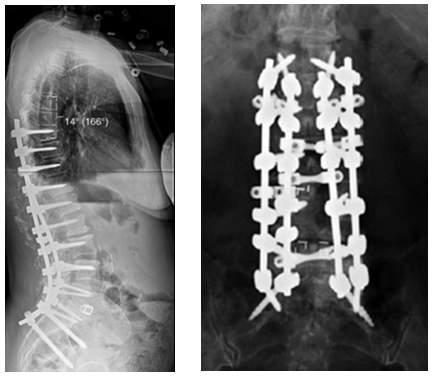

图7 术前-术后1个月-术后1个月外观

图8-11 相关文献表明,钴铬合金可提高固定强度及融合率,防止断棒,但也增加了PJK的发生率

图15 近段棒的塑形和近段交界性角度之间的不匹配也是PJK的危险因素之一

图16 矢状面失平衡过度矫正

图17 据文献报道,腰椎前凸(LL)过度矫正和SVA基线位置不当,均为增加PJK发生的风险因素